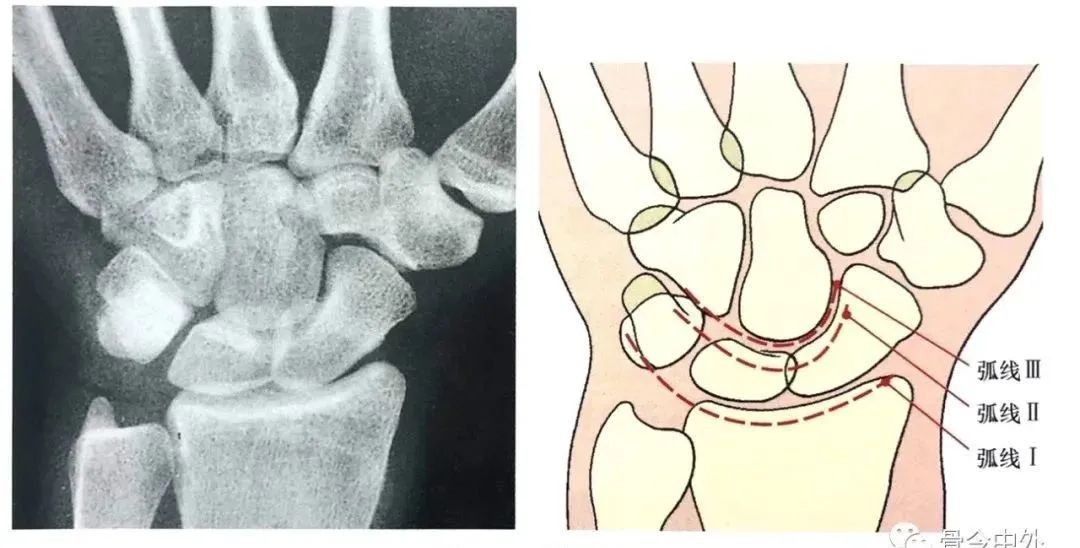

3.腕骨弧线

Gilula 提出三个平滑的弧形勾画出近侧列和远侧列腕骨。弧 I 把舟骨、月骨和三角骨近端关节面连在一起;弧 Ⅱ 勾画出上述骨远端凹面;弧 Ⅲ 由头状骨和钩骨远端凸面所形成。

图16腕骨弧。在正常腕关节背掌位X线片上3个平滑的弧线勾画出近侧列和远侧列腕骨。